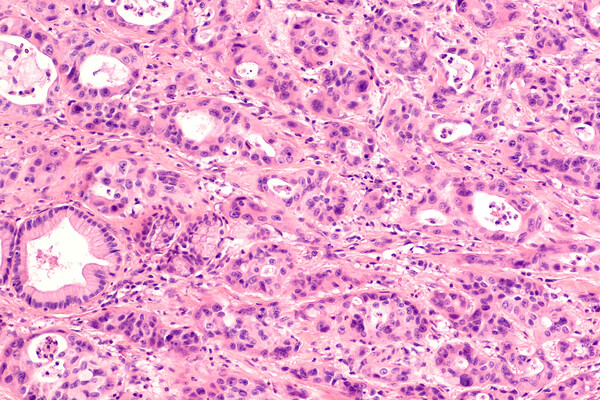

Еще одно агрессивное онкозаболевание — мелкоклеточный рак легкого. В России он занимает второе место по распространенности и первое по уровню летальности, ежегодно унося жизни около 30 тысяч человек.

По словам онколога, выживаемость при раке легкого остается низкой и напрямую зависит от ранней диагностики. Согласно статистике, если болезнь была выявлена на I стадии, то в течение года выживает 80% пациентов, тогда как при диагностике на IV стадии этот показатель снижается до 19%. Пятилетний рубеж переживают всего 2% онкобольных.

«Основной причиной развития мелкоклеточного рака по-прежнему является курение. Риск заболеть возрастает пропорционально количеству выкуриваемых сигарет и стажу курения. Однако научные исследования также подтверждают негативное влияние пассивного курения на здоровье легких, что подчеркивает важность профилактических мер в борьбе с этим недугом», — добавил специалист.